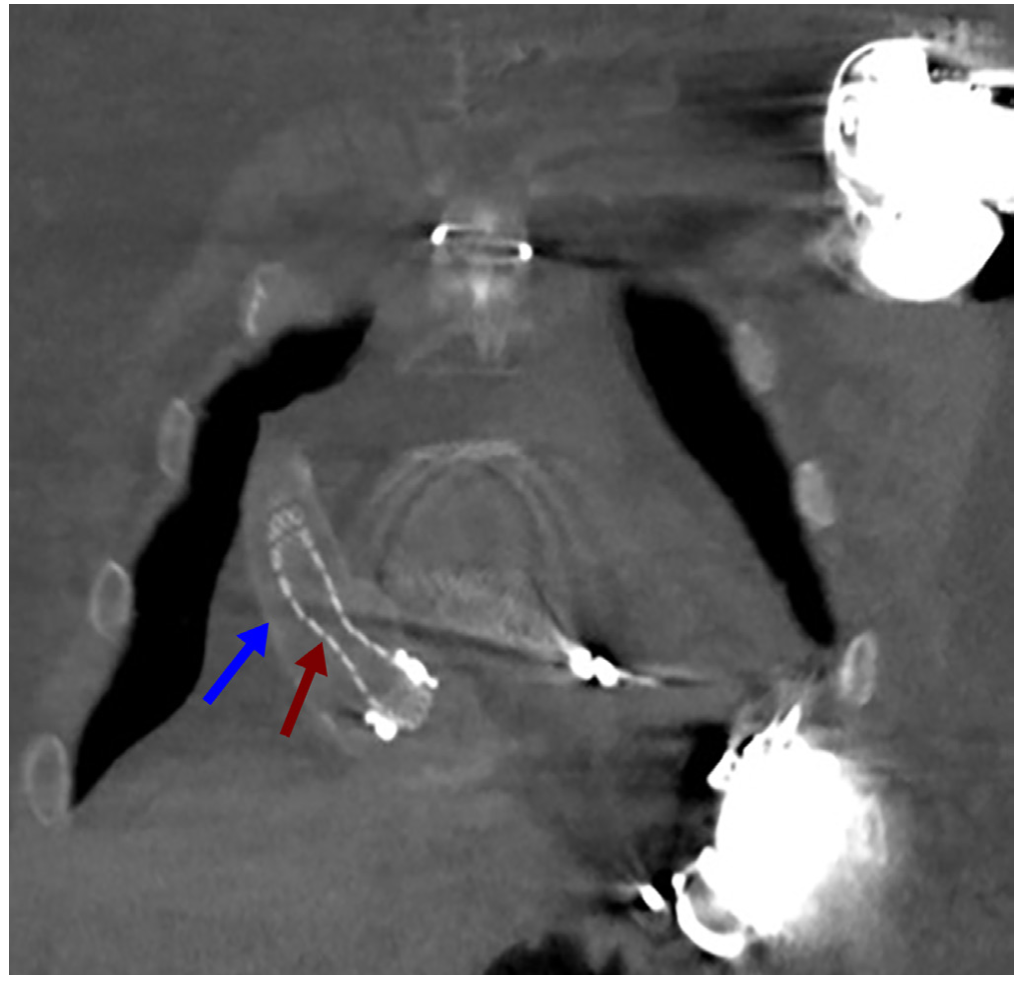

Computed tomography confirmed stenosis of the outflow graft; however, it was not able to differentiate internal vs external obstruction secondary to thrombus formation between the Gore-Tex sheet and the true outflow graft (Figure 3). A hemodynamic ramp study failed to show an increase in cardiac output or increase in left ventricular (LV) unloading, thus further supporting a hemodynamically significant obstruction. After a discussion with the multidisciplinary team, percutaneous stenting of the outflow graft was pursued.